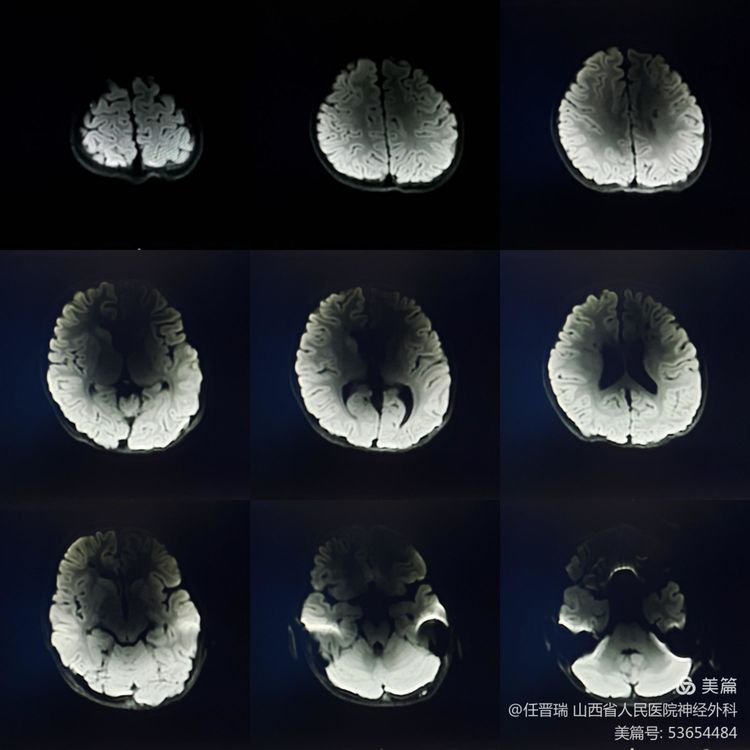

术前MR:未见新发脑梗死

术前CTP:双侧额叶低灌注